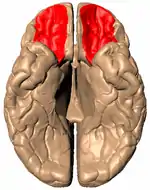

El giro orbital, destacado en rojo. | ||